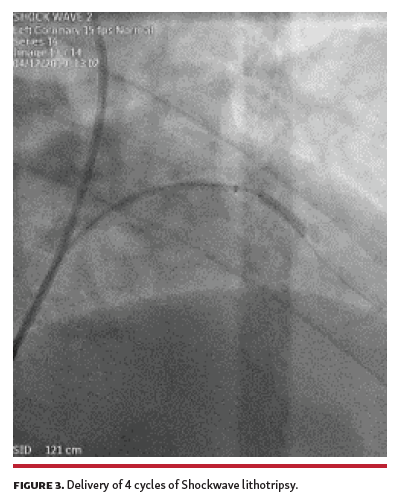

After several attempts with 2.0 x 15 mm and 2.5 x 15 mm compliant and non-compliant balloons used for predilation, a significant residual stenosis remained (Figure 2). At that time, we decided to use Shockwave intravascular lithotripsy (IVL; Shockwave Medical). A 3.00 x 12 mm lithotripsy balloon was chosen, but proved too bulky to advance and deliver. Guide-extension catheter improved support, and 4 cycles of lithotripsy were delivered, achieving full expansion (Figure 3). Subsequently, a 3.0 x 24 mm drug-eluting stent was delivered and deployed, with an optimal result (Figure 4).